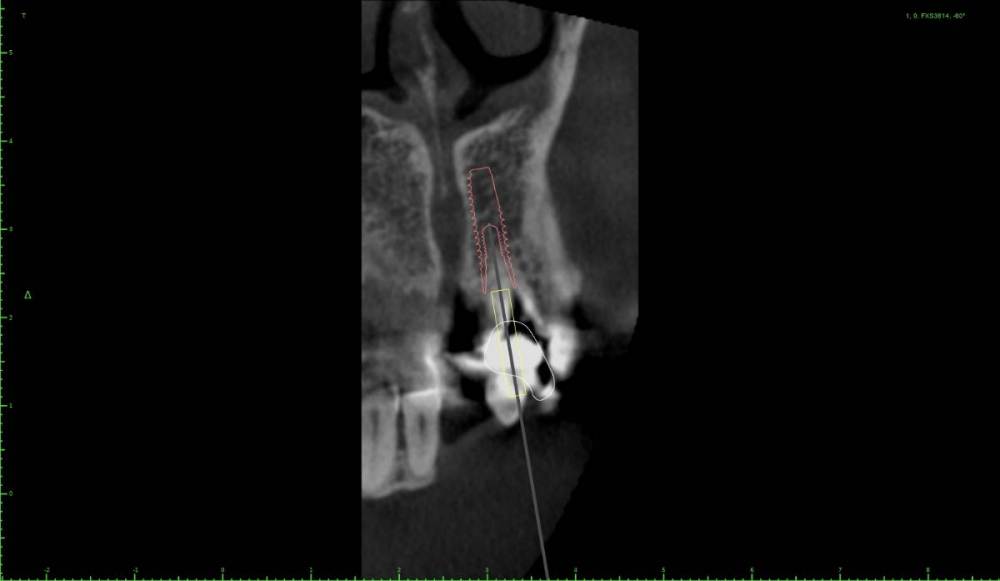

Женька Опубликовано 7 ноября, 2021 Поделиться Опубликовано 7 ноября, 2021 Сбылась мечта идиота, перебираюсь обратно в свою родную Пермь. Буду работать в найме, очень переживаю, тк работаю медленно. Будущий начальник скинул Кт, попросил поглядеть и дать вердикт. И сразу фронт, давний перелом, вестибулярная пластинка скорее всего как пергамент и отсутствие бугров верхней челюсти Я сказал, что давайте рискнем, удалим и попробуем заимплантироваться, ведь презервацию лунки мы всегда сможем сделать. Я думаю, удалить и если кортикальная сохранится то имплантация и аугментация ксено вестибулярно. Если не сохранится, то уходить на презервацию (но нужна будет мембрана в таком случае как я понимаю) и надевать капу с гарнитурным зубом. Ну и что делать с пломбировочным? Как бы поступили здесь? Ссылка на комментарий

Женька Опубликовано 8 ноября, 2021 Автор Поделиться Опубликовано 8 ноября, 2021 @Irouil можно вот так ангулировать. К бломбе близко конечно. Стоит ли бояться резцового канала и его содержимого? Ссылка на комментарий

Irouil Опубликовано 8 ноября, 2021 Поделиться Опубликовано 8 ноября, 2021 Либо не трогайте, либо уничтожьте) При такой ангуляции учитывайте два фактора 1 - мнение ортопеда 2 - срезы аксиальной проекции (полагаю, там не так много ткани, как это кажется на сагитальном срезе) Ссылка на комментарий

Карен Аванесов Опубликовано 8 ноября, 2021 Поделиться Опубликовано 8 ноября, 2021 48 минут назад, Женька сказал: @Irouil можно вот так ангулировать. К бломбе близко конечно. Стоит ли бояться резцового канала и его содержимого? Не надо ничего боятся, но надо иметь 12 и 14 мм, лучше длиннее если будут такие условия и если 4мм диаметр то остановиться на фрезе 3.6 тогда будет торк, учитывая что у дяди во рту помойка, антибиотики дней на 7 и полоскания хг на 2 мес 1 1 Ссылка на комментарий